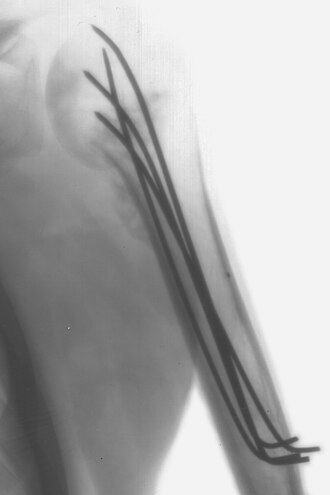

Kirschnerova žica je sterilna, glatka, ne jednom kraju zašiljena, žica koja se koristi u ortopediji i raznim drugim oblicima kirurgije čovjeka i veterini. Žice nalazimo različitih debljina (1 do 2 mm) i koriste se kako bi držale zajedno pojedine dijelove kosti ili u skeletalnoj trakciji da omoguće hvatište na kosti. U upotrebu ju je uveo Martin Kirschner, 1909.g.